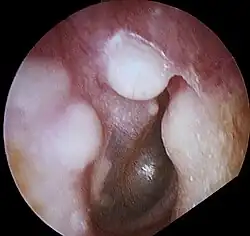

présence d'exostose dans le conduit auditif externe droit